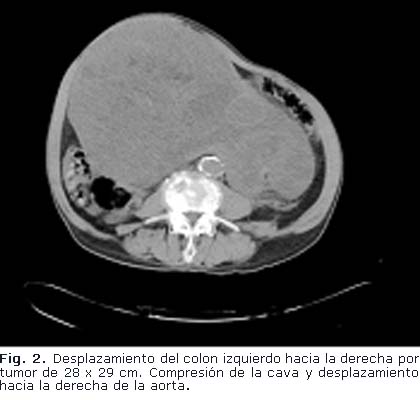

Tomografía Axial Computadorizada con contraste vía oral y endovenosa: Se aprecia gran masa tumoral compleja, que se extiende desde la excavación pélvica, donde comprime el recto hacia la derecha y la vejiga hacia delante (Fig. 2 y 3), desplaza las asas intestinales y compromete el uréter derecho, provocando hidronefrosis. El tumor mide aproximadamente 28 x 29 cm. Aorta ateromatosa, no lesión focal en hemiabdomen superior. No líquido libre en cavidad. La próstata no se logra identificar.